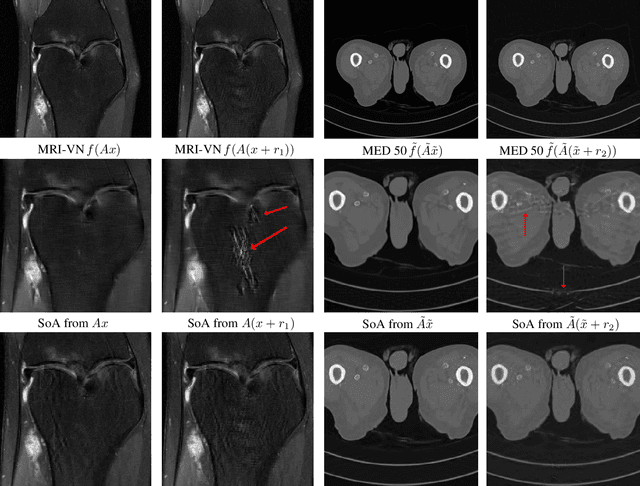

Abstract:There is overwhelming empirical evidence that Deep Learning (DL) leads to unstable methods in applications ranging from image classification and computer vision to voice recognition and automated diagnosis in medicine. Recently, a similar instability phenomenon has been discovered when DL is used to solve certain problems in computational science, namely, inverse problems in imaging. In this paper we present a comprehensive mathematical analysis explaining the many facets of the instability phenomenon in DL for inverse problems. Our main results not only explain why this phenomenon occurs, they also shed light as to why finding a cure for instabilities is so difficult in practice. Additionally, these theorems show that instabilities are typically not rare events - rather, they can occur even when the measurements are subject to completely random noise - and consequently how easy it can be to destablise certain trained neural networks. We also examine the delicate balance between reconstruction performance and stability, and in particular, how DL methods may outperform state-of-the-art sparse regularization methods, but at the cost of instability. Finally, we demonstrate a counterintuitive phenomenon: training a neural network may generically not yield an optimal reconstruction method for an inverse problem.

Abstract:Deep learning, due to its unprecedented success in tasks such as image classification, has emerged as a new tool in image reconstruction with potential to change the field. In this paper we demonstrate a crucial phenomenon: deep learning typically yields unstablemethods for image reconstruction. The instabilities usually occur in several forms: (1) tiny, almost undetectable perturbations, both in the image and sampling domain, may result in severe artefacts in the reconstruction, (2) a small structural change, for example a tumour, may not be captured in the reconstructed image and (3) (a counterintuitive type of instability) more samples may yield poorer performance. Our new stability test with algorithms and easy to use software detects the instability phenomena. The test is aimed at researchers to test their networks for instabilities and for government agencies, such as the Food and Drug Administration (FDA), to secure safe use of deep learning methods.